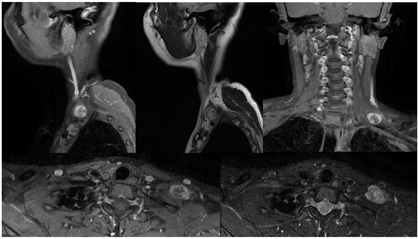

术前颈部MR平扫+增强(图1)与术前MRI-3D臂丛神经重建(图2)

颈部MR平扫+增强及臂丛神经MRI-3D重建显示左颈部占位考虑神经源性肿瘤可能性大。

对于臂丛神经鞘瘤,手术前明确诊断十分重要。由于缺乏典型的临床特征,该肿瘤的临床诊断较困难,即便是些专攻周围神经疾病的外科医生也常误诊为"肿大的淋巴结"。曾有学者等报道了2例癌症患者,在行PET-CT检查均发现在腋下或锁骨下区有高代谢的肿物,考虑为恶性肿瘤转移的淋巴结,然后行手术切除时术中才发现其来源于臂丛神经,从而考虑为臂丛神经鞘瘤[3]。除了常规的病史及体格检查外,MRI检查被认为是显示臂丛神经及其疾病较好的影像学检查方法[4]。术前常规MRI检查能清楚地显示肿瘤的部位、大小及其与臂丛神经的关系。T1加权像上肿物信号等于或略低于肌肉信号,T2加权像上肿物信号较高,可接近脑脊液信号。其注射增强剂后表现为中等度强化,但强化多不均匀。另外更进一步,本案例在常规MRI基础上对臂丛神经进行3D重建定位,使得肿瘤与臂丛神经的关系清晰可见,对于手术中神经保护有极其重要的参考价值。